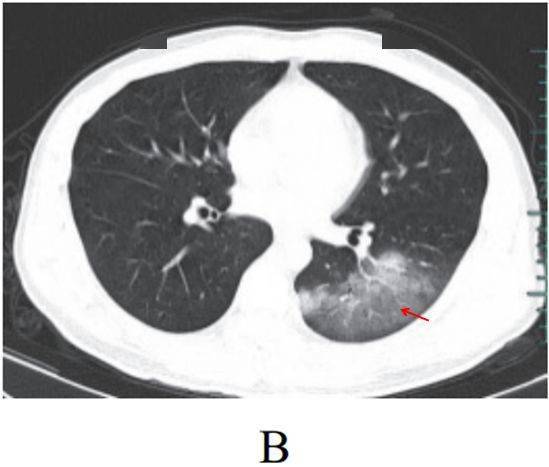

病灶形态以三种类型为主,即多叶多灶分布病灶(图 2-2A) 、单叶片状病灶(图 2-2B)和孤立性类圆形病灶(图 2-2C)

单叶片状病灶(图 2-2B)